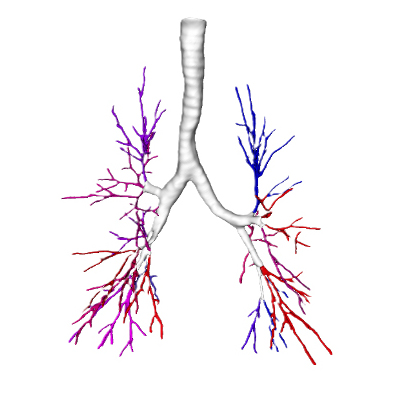

Examples of core capabilities that provide complementary detailed, procedure-relevant insights include:

- Segmentation of anatomical structures up to sub-segmental level

- Quantitative analysis of complex lung patterns and diseased regions

- Anatomical mapping to support navigation planning and guidance